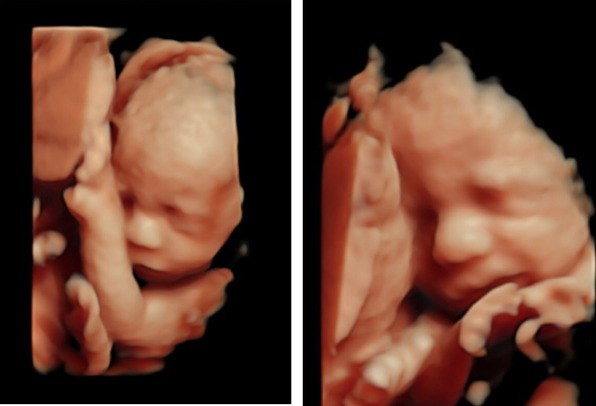

Eksempel på en 3D/4D scanning // Foto: Hjertelyd

Hjertelyd, en dedikeret klinik specialiseret i graviditetsscanninger, står klar til at skabe uforglemmelige øjeblikke for kommende forældre. Uanset om man søger tryghed, ønsker at følge nøje med i barnets udvikling, eller blot er nysgerrig efter kønnet, tilbyder Hjertelyd professionelle scanninger i 2D, 3D og 4D.